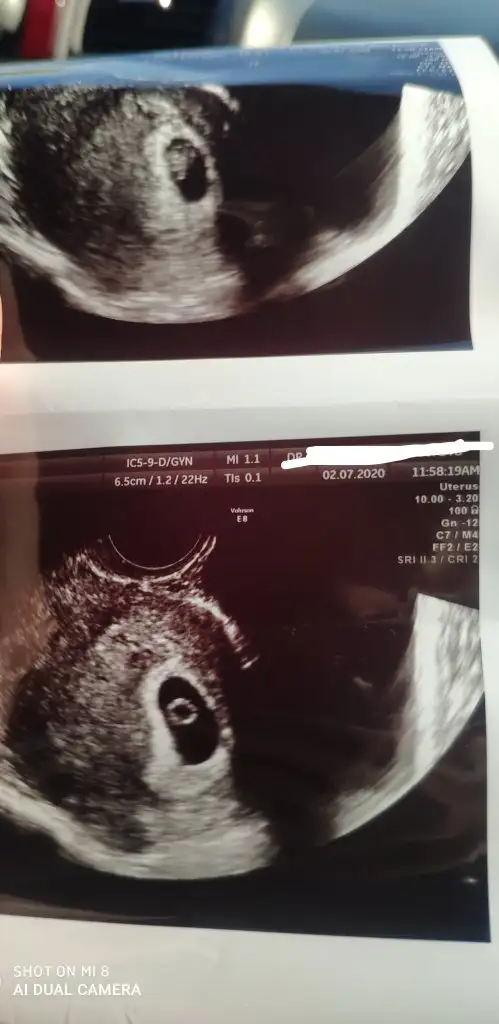

Buna göre kız gibi en iyi 11 12 13 hafta olmalı saglıkla gelsib minnoşTahmin yapabilir misiniz kızlar. İlk evladimiz olacak inşallah merak ediyorum cinsiyet fark etmiyor ama insan dayanamıyor. 7. Hafta vajinal ultrasonEki Görüntüle 2658454